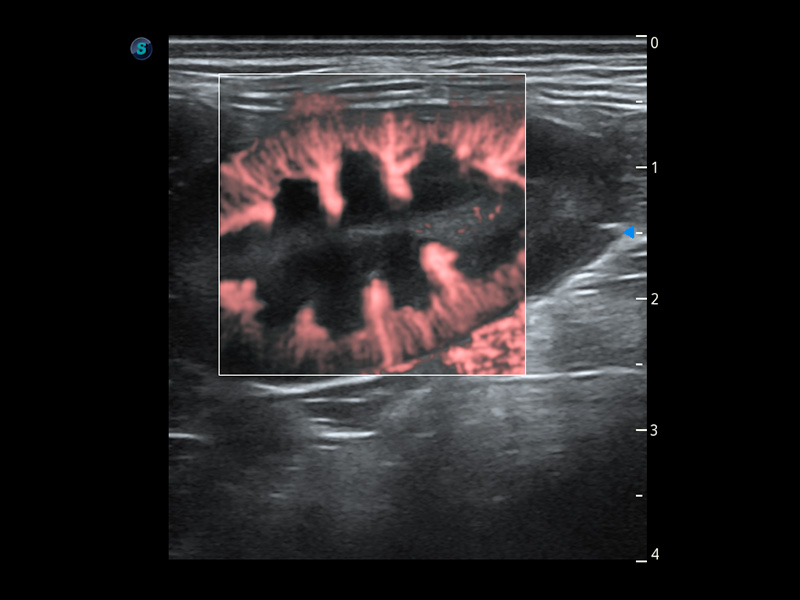

ProPet 60 作为一款高端台式动物超声设备,为动物医生的日常诊断提供了一系列贴合动物临床需求、解决临床实际问题的高级成像功能。凭借全系列高清探头,满足医生对腹部、心脏、生殖、浅表、肌骨等成像的所有需求,切实帮助您提升检查效率,提高诊断信心。

动物是人类最亲密的朋友和最值得信赖的伙伴。百老汇电子游戏官网也一直致力于探索动物专用的超声影像解决方案。 全新推出的ProPet系列,是百老汇电子游戏官网在动物超声影像智能化、专业化、精准化的一次跨越式革新。动物不能用言语来表述自己的不适,通过超声影像,ProPet系列搭建了动物医生与不同物种沟通的“桥梁”,为动物医生注入了“治愈之力”。